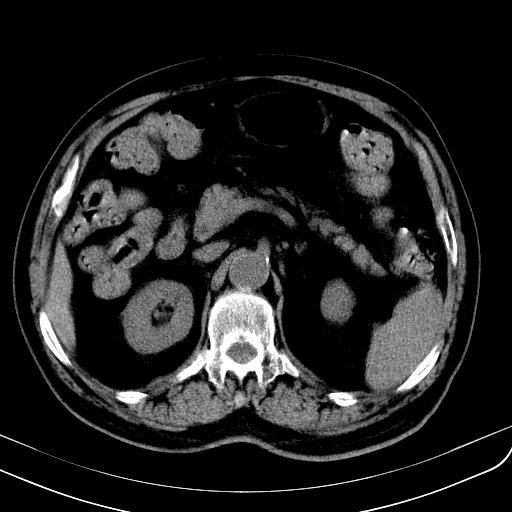

胃底靠近胃大弯处可见一圆形软组织影,直径为3.45cm,ct值约为30.1hu

边缘光滑,密度均匀,良性占位,首先考虑平滑肌瘤。